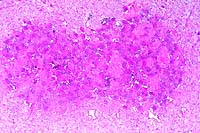

- Iliac, subvertebral mass: There is a dense fibrous capsule

of some section borders which contains individualized and flattened

bone multifocally. There is abundant, moderately cellular stroma

with flattened to plump spindle cells and abundant mature collagen.

Multifocally, there is a lightly basophilic matrix that stains

with alcian blue for mucopolysaccharide. Scattered foci of more

dense homogenous eosinophilic stroma with embedded nuclei are

noted. There are discrete islands of multinucleate giant cells

that have approximately 6 to up to 30 nuclei, and abundant eosinophilic

cytoplasm. These cells surround and are occasionally found within

small non-muscular vessels. The cytoplasm occasionally contains

iron positive hemosiderin material, or has small cleft-like vacuoles.

These latter cells often have light blue staining of the cytoplasm

with alcian blue. The vessels are variably congested, with some

small foci of hemorrhage and a few hemosiderophages. Trichrome

staining reveals abundant collagen throughout, positive staining

in more homogenous stromal areas, and occasionally centrally

around multinucleate giant cells.

- Case 20-3. Tumor. Normal bone is replaced by streams

& bundles of spindle cells and multifocal clusters of multinucleate

giant cells.